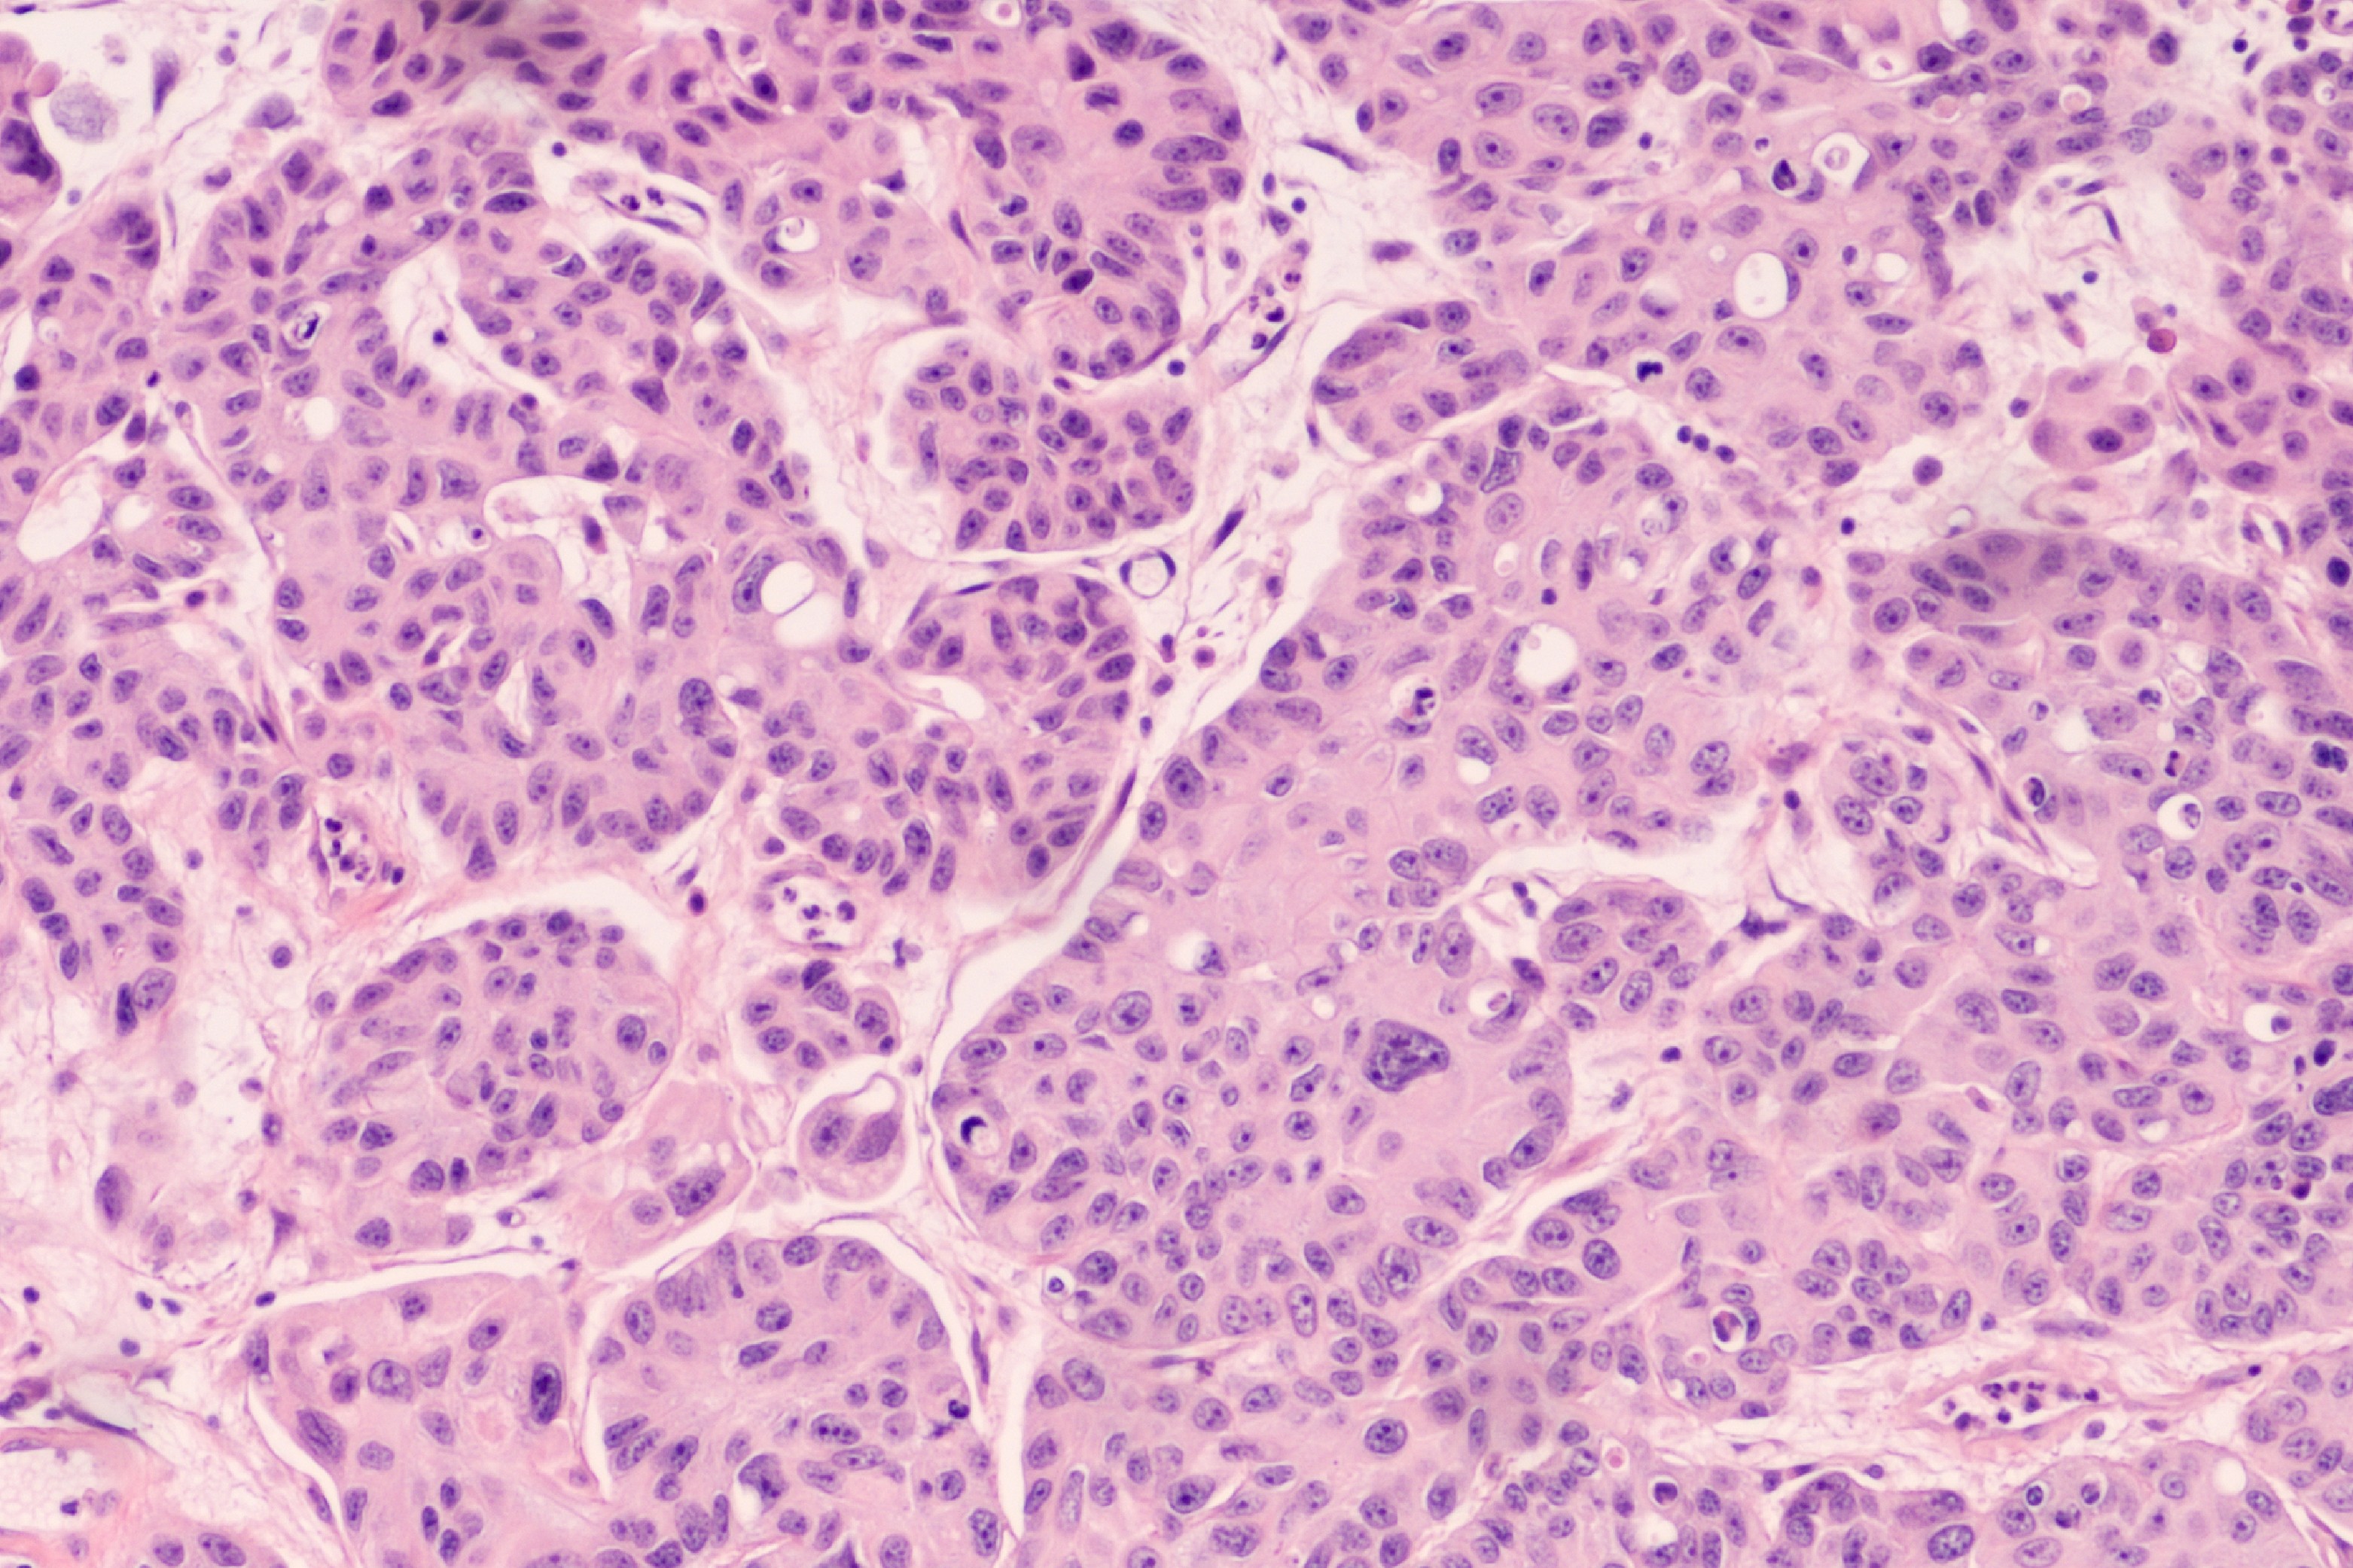

Существенной проблемой, возникающей при использовании в онкологии практически всех лекарственных препаратов, является развитие эффекта приобретенной лекарственной устойчивости к ним, что приводит к уменьшению их терапевтической эффективности. Особое значение этот эффект имеет для противоопухолевых химиотерапевтических соединений, поскольку может привести к прогрессированию онкологических заболеваний и гибели пациентов. В ходе работы было обнаружено, что развитие резистентности к Цисплатину сопряжено с различными изменениями метаболизма глюкозы, аминокислот и липидов. При этом эти модификации могут быть различными. Так, например, часть устойчивых клеток переходят на преимущественно гликолитическое окисление глюкозы, в то время как в других линиях отмечается усиление окислительного фосфорилирования и снижение активности гликолиза.